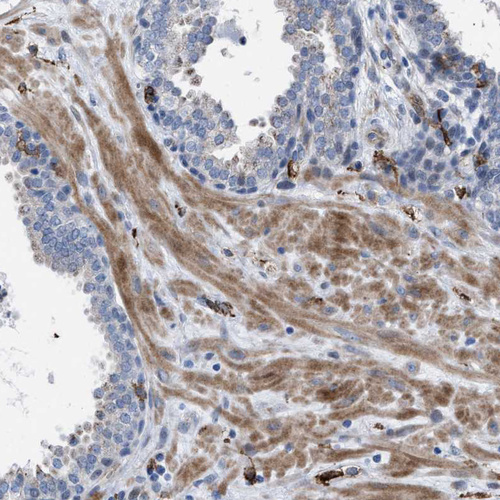

Immunohistochemical staining of human kidney shows strong membranous positivity in cells in tubules.